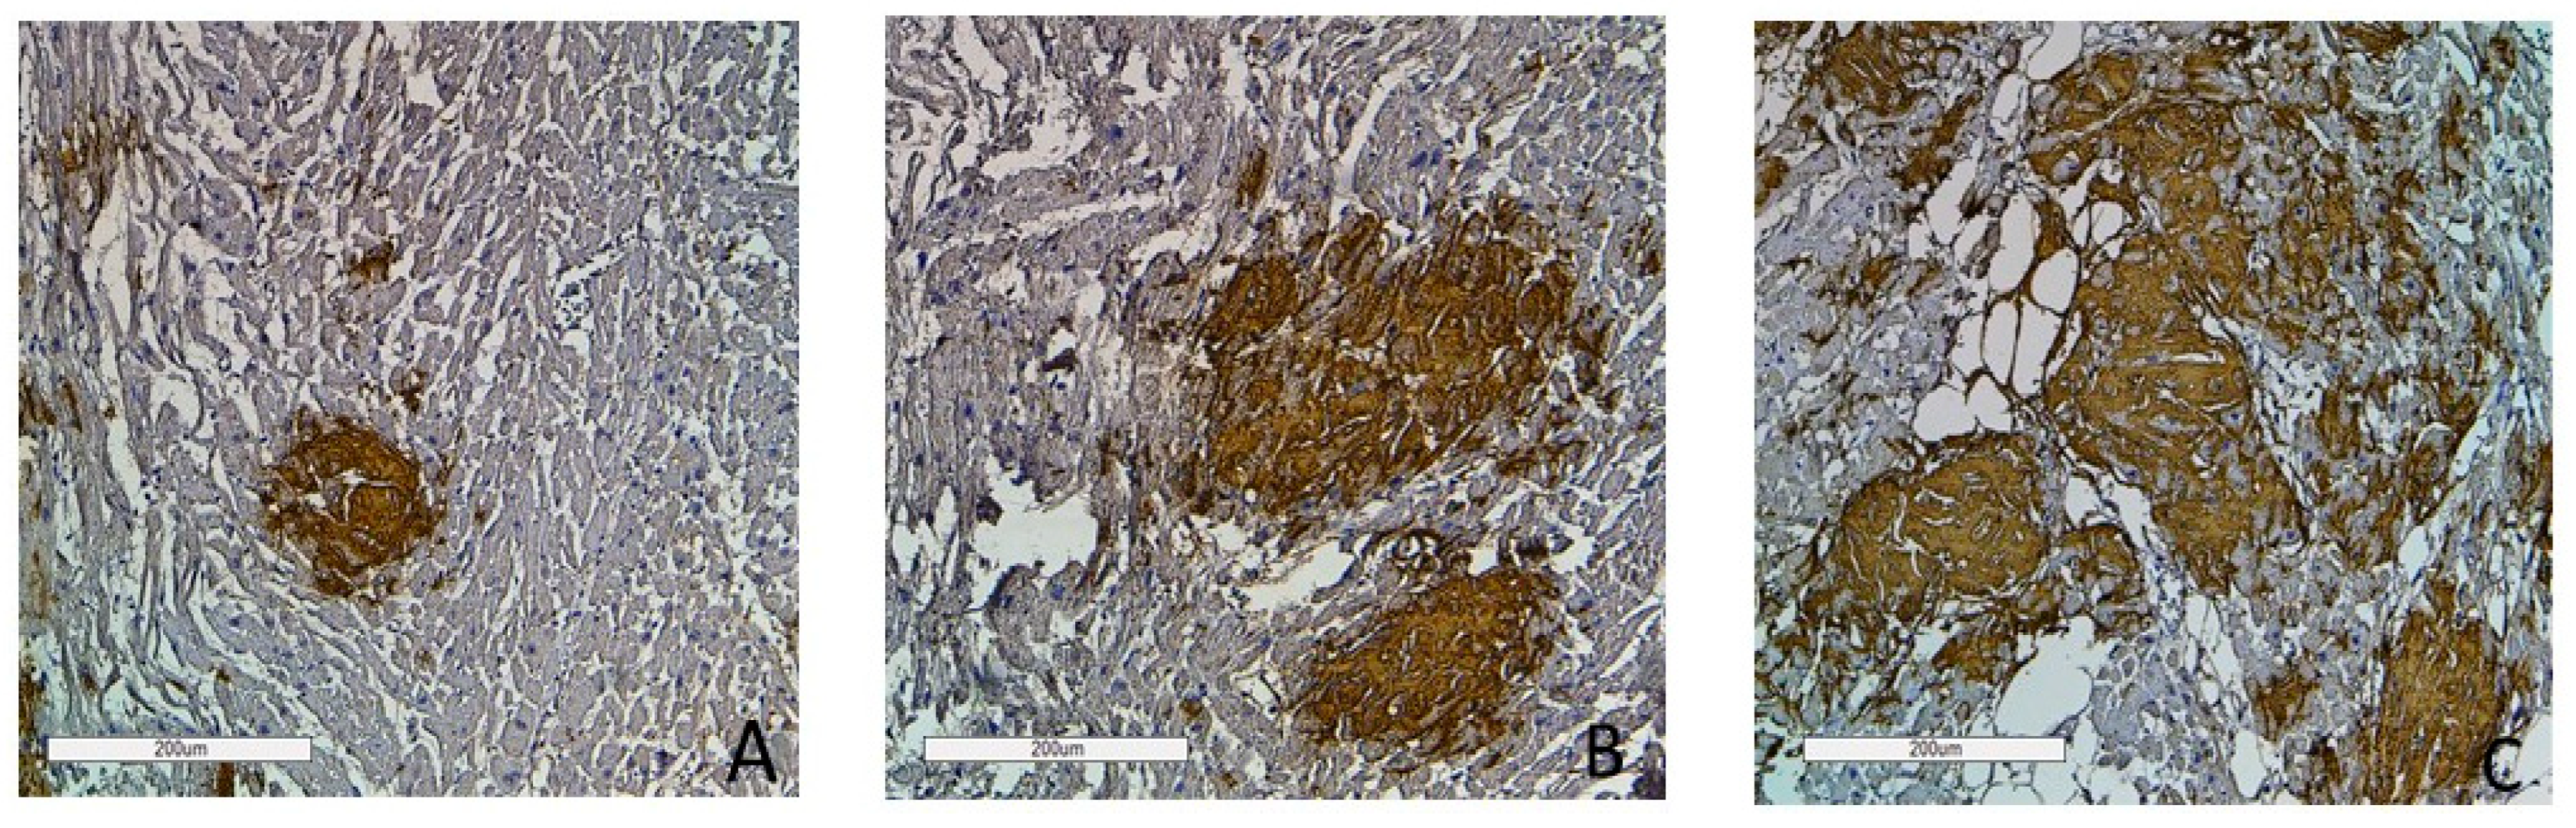

2.3. The Degrees of Amyloid Deposition

To assess the intensity of amyloid deposits in biopsy and autopsy specimens, a grading system was used with three grades of amyloid depositions (Grade 1—0–20% in the field of vision; Grade 2—20–40%; Grade 3—40% and over) based on the clinical significance of the 20% myocardial lesion threshold [2]. The findings demonstrate that the most intense amyloid depositions both in biopsy and autopsy specimens occurred in patients with AL kappa amyloidosis. No cases with Grade 1 amyloid depositions were identified, while Grade 3 depositions were the most common findings (78%). Grade 2 depositions were recorded in 22% of the studied cases. Among the cases of AL lambda amyloidosis, Grade 1 amyloid depositions were found in 19%, Grade 2 in 30% and Grade 3 depositions in 51% of the deceased persons. Most patients with ATTR amyloidosis had amyloid depositions of Grade 2 (42%). Grade 1 was found in 38% and Grade 3 in 20% of cases. In the AA amyloidosis group, the largest proportion of patients had amyloid depositions of Grade 1 (59%), while Grade 2 was identified in 35% and Grade 3 only in 6% of cases (Figure 8 and Figure 9).

To assess the intensity of amyloid deposits, a semi-quantitative grading system was used with three grades of amyloid depositions, as follows: Grade 1—amyloid deposition made up less than 20% in the field of vision; Grade 2—20–40%; Grade 3—40% and over.

Figure 9. Immunohistochemistry images of amyloid deposition in the myocardium. Grade 1 (0–20% of amyloid deposits) (A); Grade 2 (20–40% of amyloid deposits) (B); Grade 3 (more than 40% of amyloid deposits) (C). Amyloid is stained with polyclonal antibody to Prealbumin, ×100.